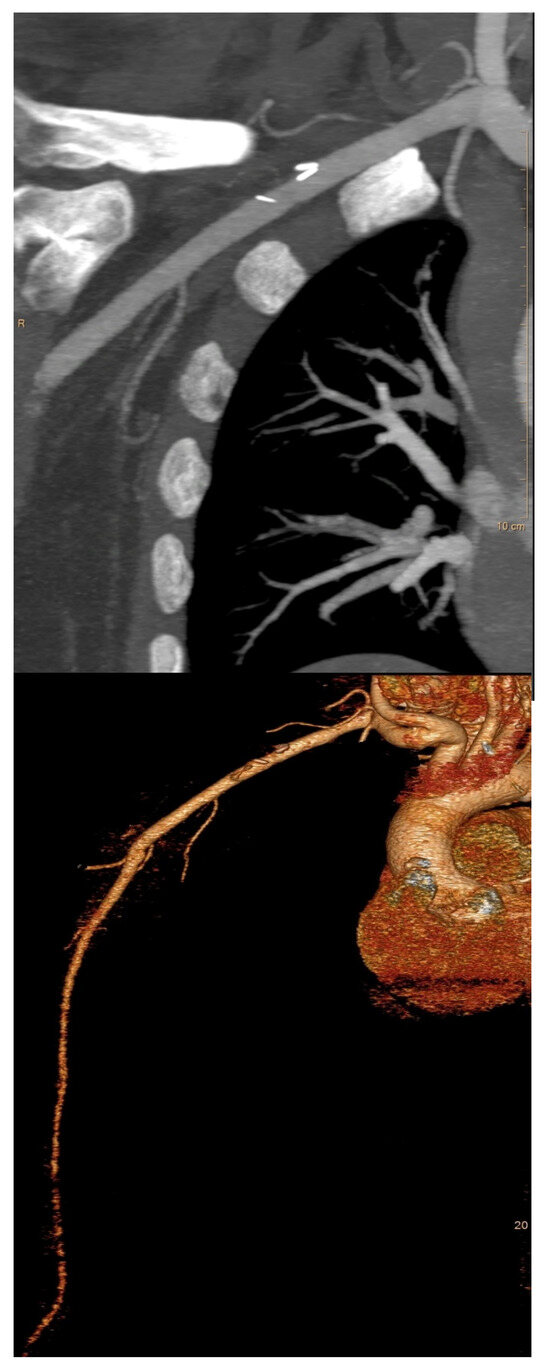

2.2. Preoperative Evaluation